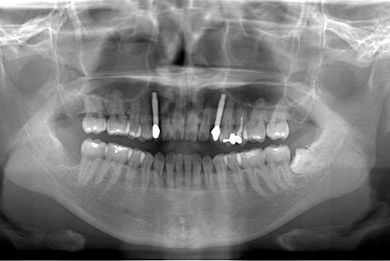

治療内容 インプラント2本、メタルボンドセラミッククラウン2本

治療後

• 治療後